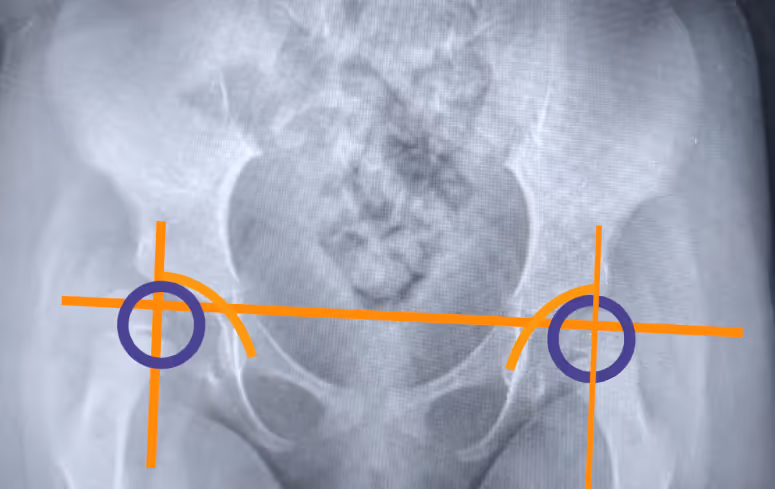

Диагноз ставит врач на плановом осмотре. Не все изменения в тазобедренных суставах можно увидеть на УЗИ, поэтому пациентам со СМА рекомендуется делать рентгенографию — по снимку врач определяет состояние суставов и решает, какие меры принимать.

Небольшое смещение головки бедренной кости, подвывих, полный вывих — все эти изменения ещё называют дисплазией тазобедренного сустава.

Да, но тут важны нюансы. Действительно, при подвывихах бедренных костей без других сопутствующих заболеваний ребенка не рекомендуется вертикализировать, чтобы не спровоцировать вывих. Однако для пациентов со СМА позный режим и вертикализация в том числе — важнее. Если есть угроза вывиха, вертикализацию проводят с отведением бедер — так и улучшается положение головок бедренных костей, и создается правильная нагрузка на сустав, способствующая его стабильности [2]. Степень отведения и другие настройки системы для стояния определяет специалист.